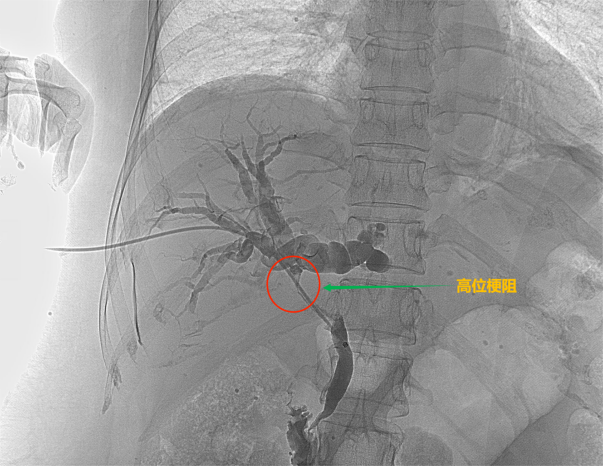

根据梗阻位置的不同可以分为低位胆道梗阻和高位胆道梗阻

高位胆道梗阻

高位胆道梗阻支架置入